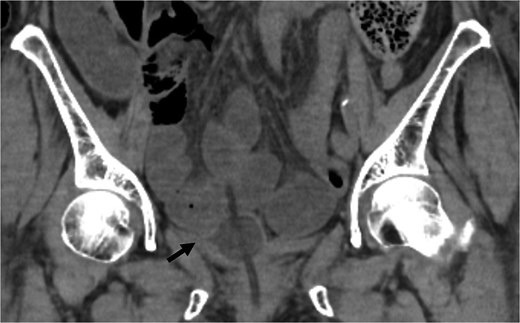

An 82-year-old female with a history of cervical carcinoma presented to our hospital with lower abdominal pain. She had undergone a total hysterectomy decades ago for cervical carcinoma, followed by radiotherapy to the pelvis. Computed tomography (CT) revealed small bowel obstruction attributable to adhesions. The patient was initially diagnosed with adhesion-related small bowel obstruction and was managed conservatively with fasting and intravenous fluid replacement. Although her bowel function promptly recovered within a few days, urinary retention of unknown etiology was noted during hospitalization, necessitating clean intermittent catheterization. When this approach proved insufficient for relieving her symptoms, an indwelling urinary bladder catheter was inserted. Two days after insertion of the catheter, a follow-up abdominal X-ray was performed to confirm recovery of her bowel movement. Imaging revealed indwelling intra-abdominal air above the liver, which was confirmed by emergency computed tomography, raising the suspicion of gastrointestinal perforation (Figs 1 and 2). Clinically, her vital signs were stable, with a heart rate of 65 beats per minute, blood pressure of 113/72 mmHg, and body temperature of 36.6°C, and her abdomen was soft and flat with slight tenderness in the lower abdomen. Laboratory evaluation indicated a C-reactive protein level of 2.31 mg/dl and leukocytes of 5100/mm3. Emergency laparotomy was performed under general anesthesia to rule out potentially life-threatening conditions, such as gastrointestinal perforation. Intra-operatively, perforation of the urinary bladder was identified, with the urinary catheter protruding through the defect (Fig. 3). The bladder wall was extremely thin and fragile, suggesting significant loss of compliance. The bladder rupture was repaired using a two-layer closure with absorbable sutures, and the urinary catheter was repositioned to ensure proper drainage. The patient’s postoperative recovery was uneventful, and she was discharged on postoperative day 25 with the urinary catheter in situ. She was followed up for 70 days, and no signs of intra-abdominal leakage were observed on cystography. The catheter was removed without further complications.

Coronal CT showed the urinary catheter was mispositioned outside the bladder (arrow).

The diagnosis of bladder rupture can be particularly challenging in cases with atypical presentations. In this patient, the presence of intra-abdominal air initially led to the suspicion of gastrointestinal perforation, although the mild abdominal tenderness was atypical for this condition. Retrospective analysis revealed that the urinary catheter had been mispositioned outside the bladder after penetrating the bladder wall, further complicating the clinical picture. This highlights the importance of considering bladder rupture in the differential diagnosis of patients with a history of pelvic irradiation presenting with intra-abdominal air and nonspecific symptoms.